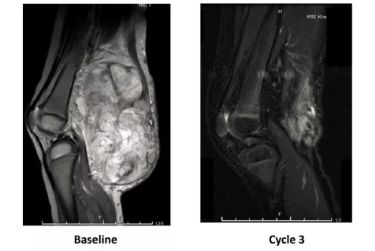

这是另外一个得这个病的孩子,他有一个非常大的肿瘤长在他的关节的地方。以前这样的孩子,刚才说了,要不就放弃,要不就截肢,看看怎么样。即使截肢依然有可能不行,因为外科手术没有办法切除这个肿瘤。

用了新药以后,两三个疗程以后,它就控制住了。没有完全消失,但这个时候,外科医生就可以做一个非常干净的切除术,把它切掉。这就是新药的力量。